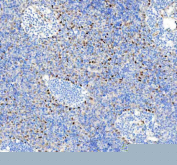

IHC staining of FFPE human spleen tissue with Phospho-HSF1 antibody. HIER: boil tissue sections in pH8 EDTA for 20 min and allow to cool before testing.